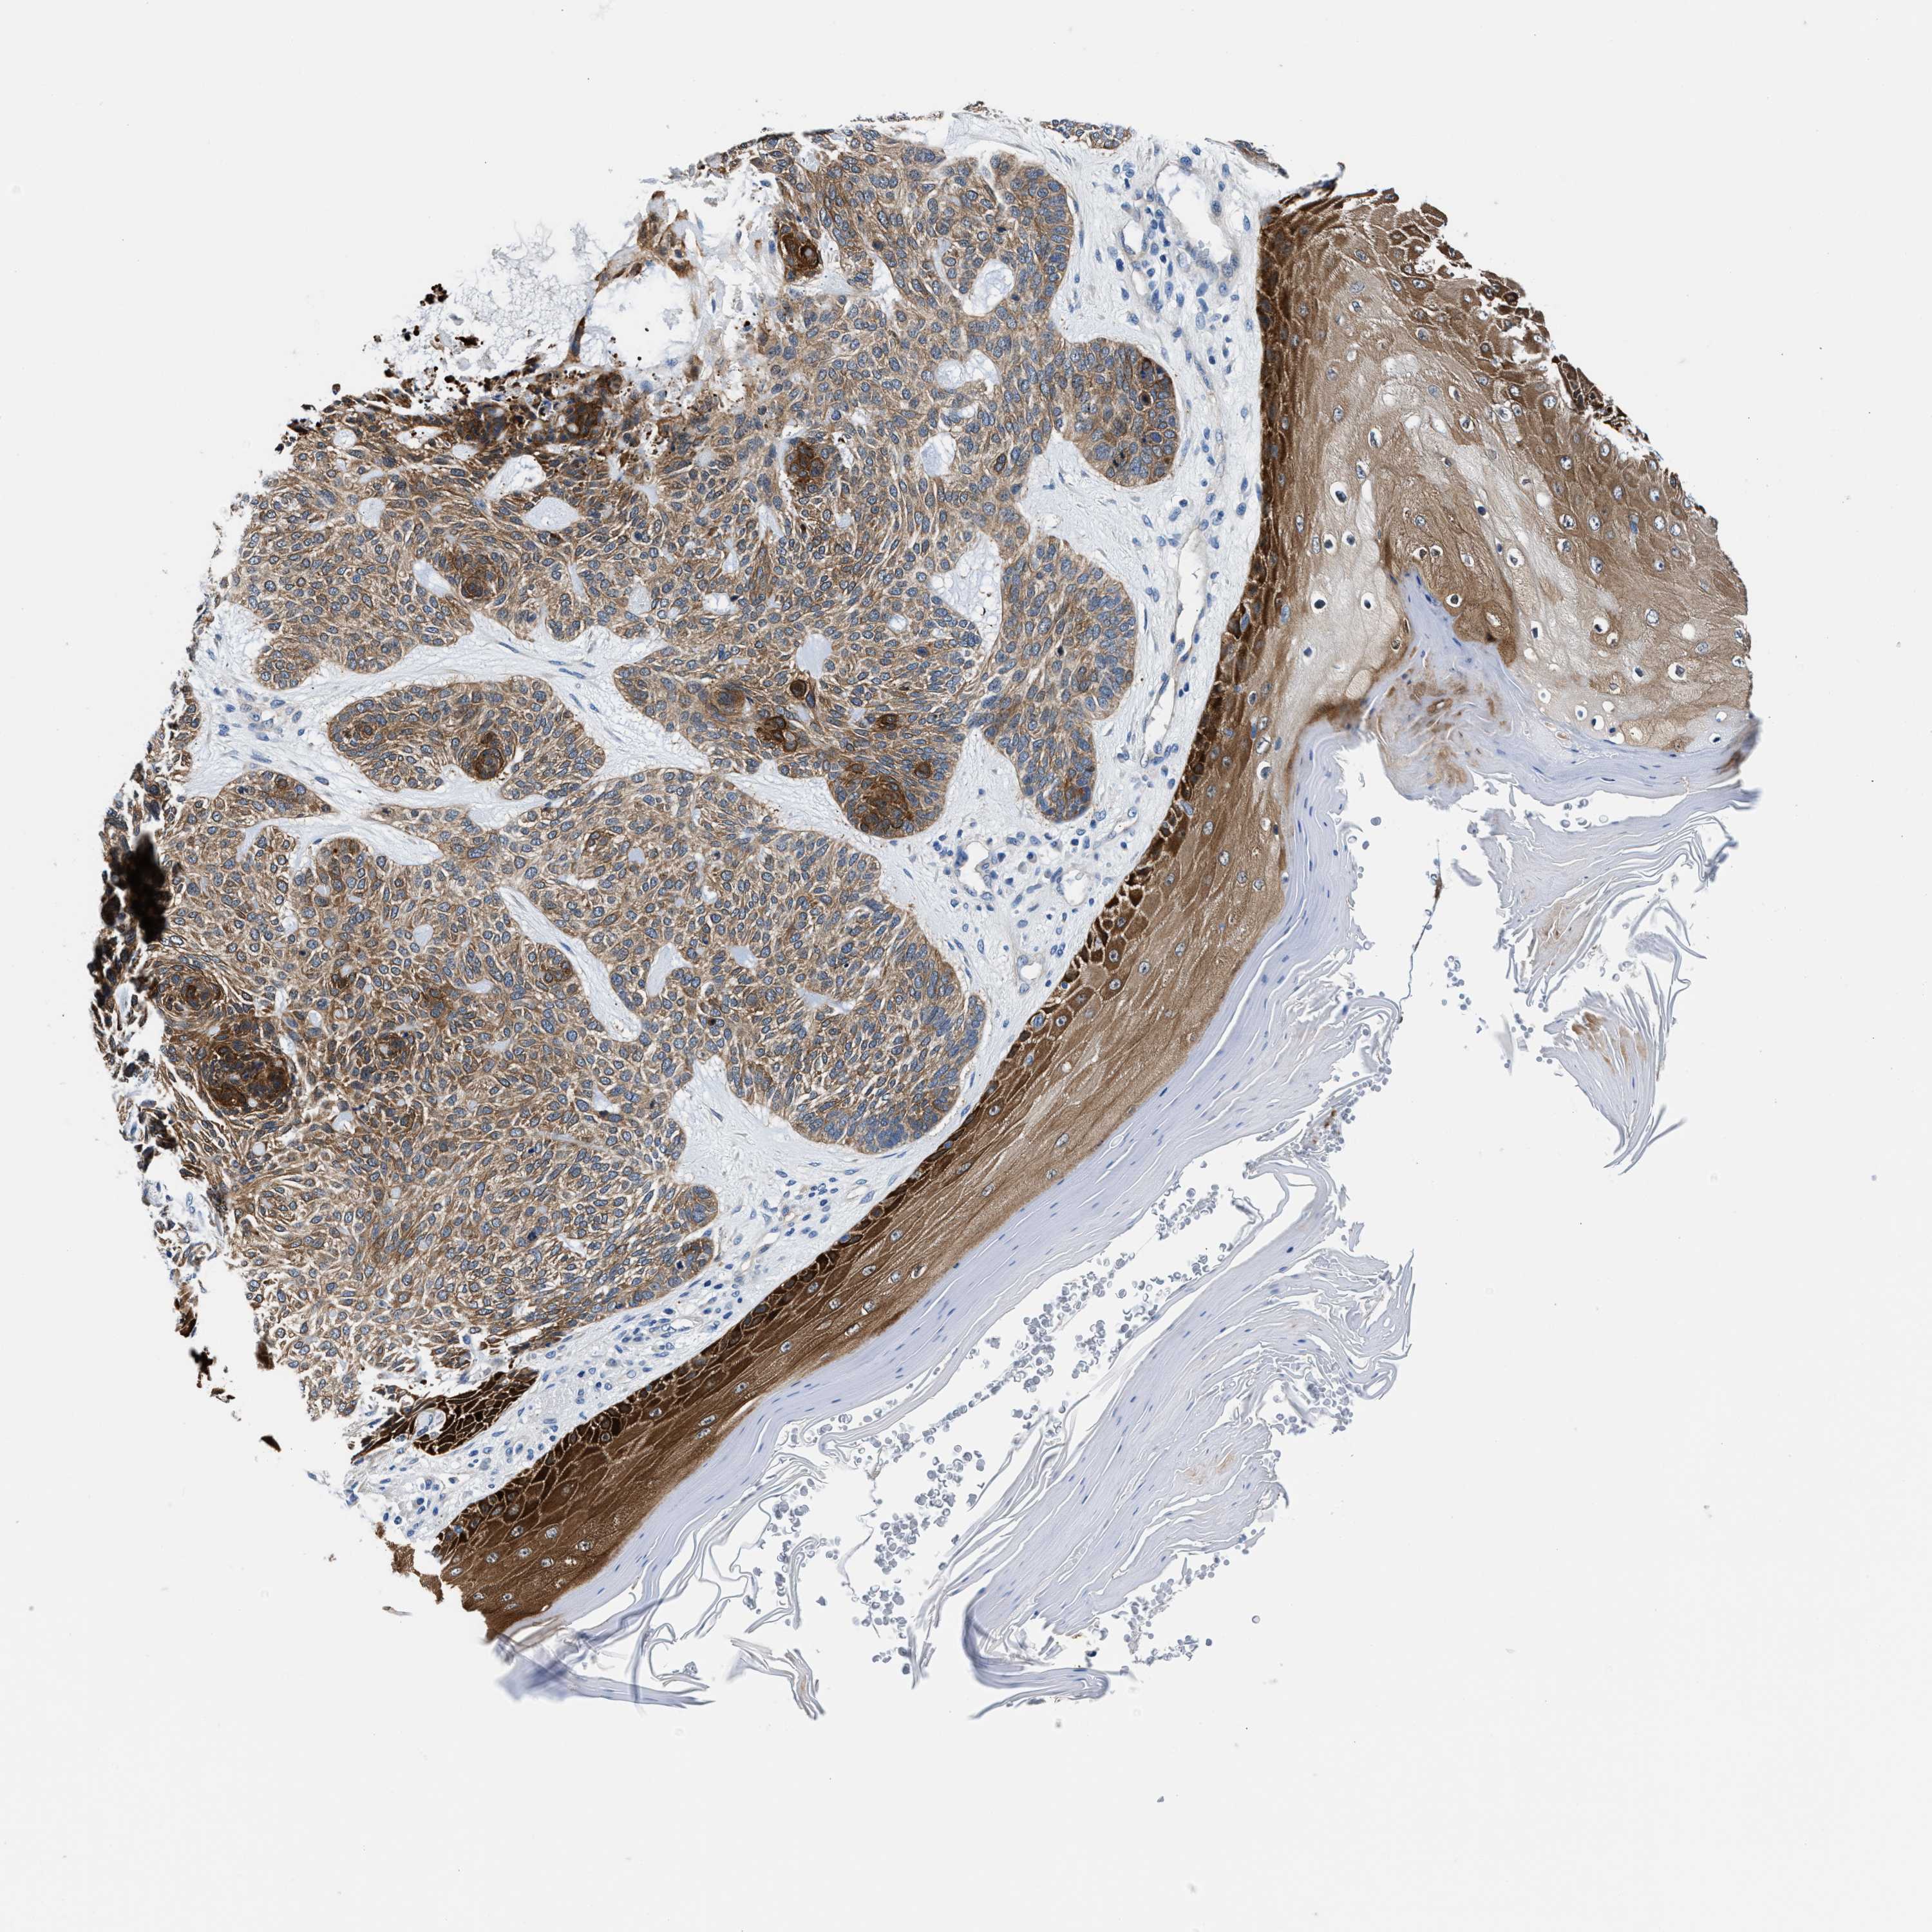

Basal cell and squamous cell cancer

SKIN CANCER - Protein expressioni

A mouse-over function shows sample information and annotation data. Click on an image to view it in a full screen mode. Samples can be filtered based on level of antibody staining by selecting one or several of the following categories: high, medium, low and not detected. The assay and annotation is described here.

Antibody stainingi

Antibody staining in the annotated cell types in the current human tissue is reported as not detected, low, medium, or high, based on conventional immunohistochemistry profiling in selected tissues. This score is based on the combination of the staining intensity and fraction of stained cells.

Each image is clickable and will lead to virtual microscopy that enables deeper exploration of all samples and also displays staining intensity scores, fraction scores and subcellular localization as well as patient and tissue information for each sample.

Antibody HPA021819

Staining

High

Medium

Low

Not detected

Intensity

Strong

Moderate

Weak

Negative

Quantity

>75%

75%-25%

<25%

None

Location

Nuclear

Cytoplasmic/membranous

Cytoplasmic/membranous,nuclear

Squamous cell carcinoma, NOS